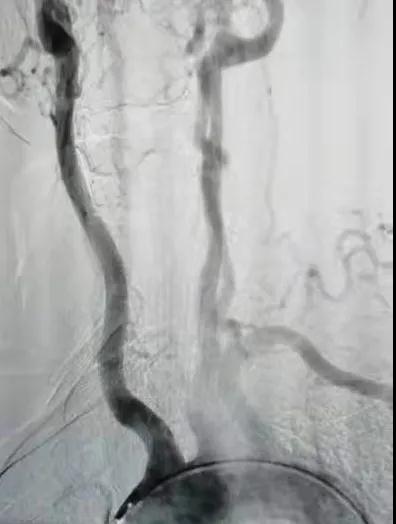

2.jpg

右鎖骨下動脈未顯影